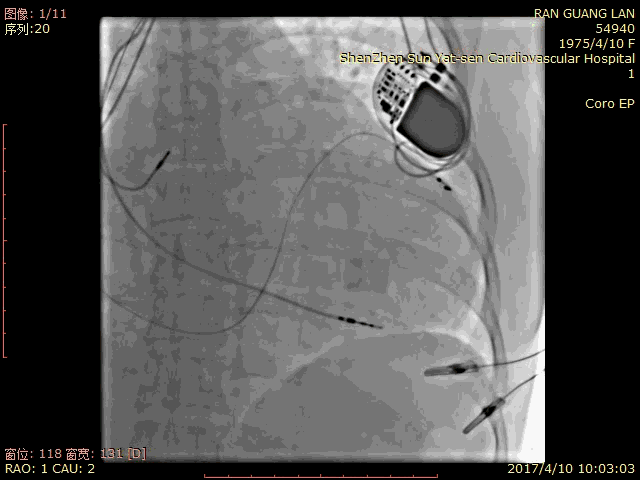

病例一

Metronic 4296 双阴极电极,6248辅助鞘

手术过程